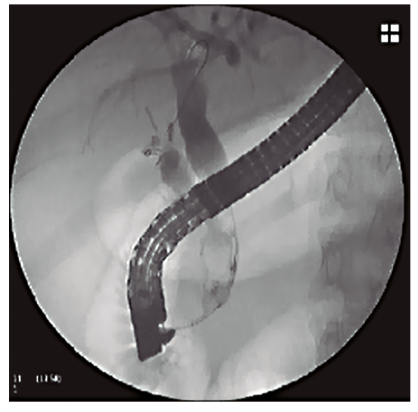

Se trata de una paciente de 47 años, con antecedente de colecistectomía laparoscópica dos años antes y posterior CPRE por litiasis residual, que ingresó por un cuadro de síndrome coledociano. Al ingreso presentaba ictericia cutáneo-mucosa asociada a dolor abdominal leve en la región epigástrica, sin signos clínicos de colangitis. Los datos de laboratorio arrojaron los siguientes resultados: hematocrito 42%, hemoglobina 14,1 g%, glóbulos blancos 7.100/mm3, bilirrubina total: 5,4 mg%, bilirrubina directa: 4,5 mg%, fosfatasa alcalina: 404 U/l, TGP: 223 U/l y TGO: 99 U/l. La colangiorresonancia magnética (CRM) mostró una dilatación de la vía biliar extrahepática con una imagen de defecto de señal en el colédoco distal, compatible con litiasis coledociana. Debido al hallazgo se decidió realizar una CPRE. En el procedimiento se identificó la papila con signos de papilotomía previa, se canuló la vía biliar con papilótomo y alambre guía. Con la colangiografía se evidenció una vía biliar extrahepática dilatada, de aproximadamente 13 mm, y una imagen negativa de 13 mm de diámetro en el colédoco distal. Debido a que la papila no presentaba mayor margen de corte, se decidió realizar una dilatación papilar con un balón tipo CRE de 10 mm. Posteriormente se logró la extracción del cálculo y de barro biliar con un balón extractor (Figura 1).